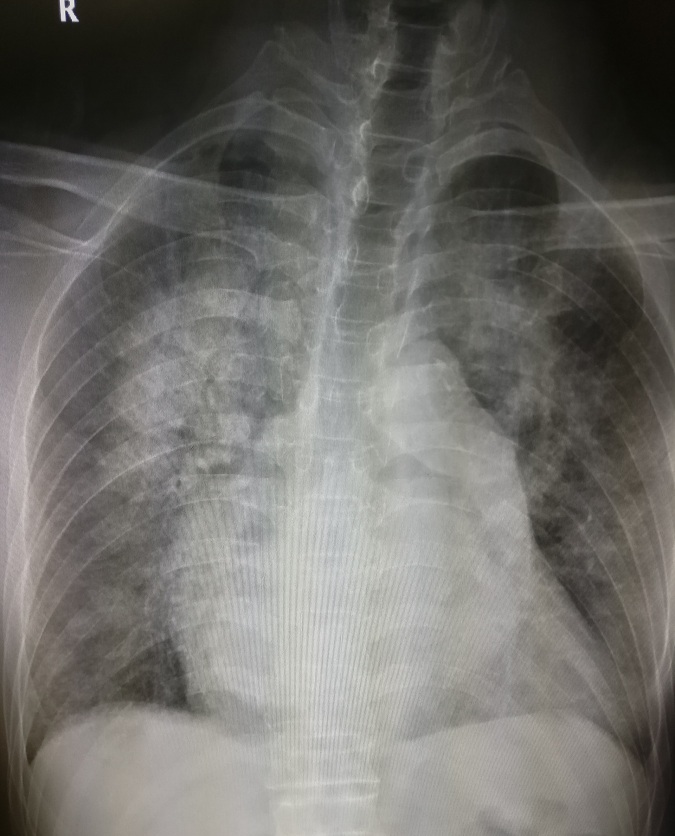

3.左心房增大

常见于二尖瓣病变特别是二尖瓣狭窄、左心衰竭、先心病如室间隔缺损等。见图3。

图3 二尖瓣换人工瓣膜后,左房增大